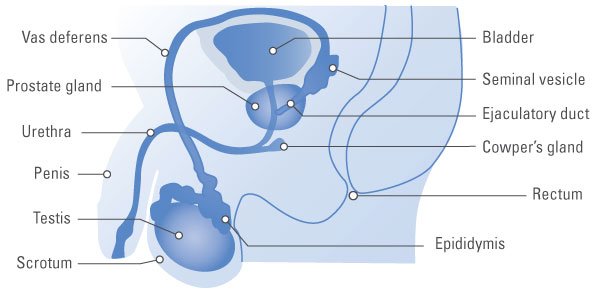

A fiatal férfi a prosztata körülbelül akkora, mint egy dió, de egyre nagyobb a korral. A prosztata ül a húgyhólyag alatt, körülveszi a felső része a húgycső. Vizelet halad keresztül a húgycső úton a hólyagból a pénisz.

Egy oldalról mutatja a fő részeit a férfi reproduktív rendszer